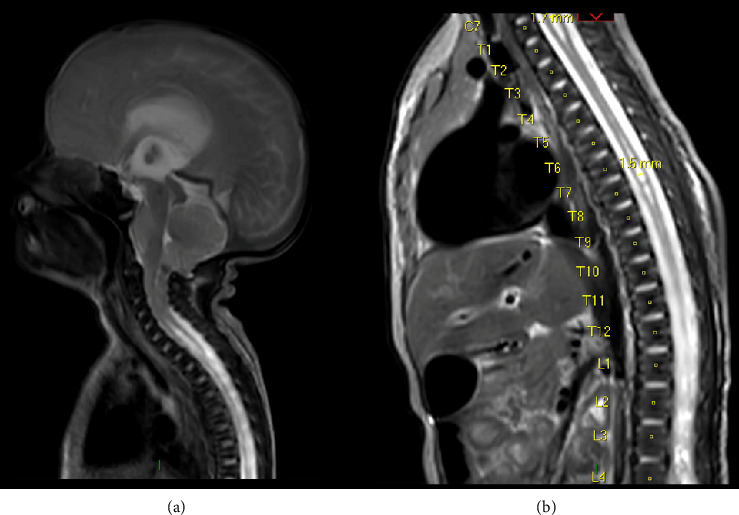

脊柱裂,特别是脊膜膨出,与自主神经功能障碍之间的联系是已知的,尽管罕见。本病例突出了脊髓脊膜膨出患儿继发的严重呼吸损害。我们描述了一个新生儿谁经历了严重的呼吸功能障碍后,成功的腰骶髓脊膜膨出修复在生命的第一天,在产前诊断为Arnold-Chiari II型畸形和先天性脑积水的背景下。此外,患者被发现有偶发脉络膜丛乳头状瘤,并在枕骨大孔减压术中切除。即使在多次成功的神经外科干预后,患者仍经历了多次需要插管和通气的呼吸暂停发作,并延长了重症监护病房的住院时间。尽管呼吸暂停-缺氧发作的频率异常高且严重,但患者表现出与年龄相适应的认知发展,现在通过气管切开术进行了夜间通气。围绕这些患者的多学科护理、呼吸窘迫的管理以及本病例的不同病因,我们可以吸取经验教训。尿路感染发作与呼吸暂停发作频率增加之间也存在相关性,这就提出了一个问题,即在有重要手术史的背景下,该患者的膀胱刺激是否部分触发了自主神经反射障碍。

The association between spina bifida, specifically myelomeningocele, and autonomic dysfunction is known although rare. This case highlights the severe respiratory compromise that can occur in paediatric patients secondary to myelomeningocele. We describe a case of a neonate who experienced profound respiratory dysfunction following a successful lumbosacral myelomeningocele repair on Day 1 of life, on the background of a prenatal diagnosis of Arnold-Chiari Type II malformation and congenital hydrocephalus. In addition, the patient was found to have an incidental choroid plexus papilloma which was resected along with foramen magnum decompression. Even after multiple successful neurosurgical interventions, the patient experienced a number of apnoeic episodes requiring intubation and ventilation and a prolonged intensive care unit stay. Despite the exceptionally high frequency and severity of the apnoeic-hypoxic episodes, the patient is demonstrating age-appropriate cognitive development and is now ventilated overnight via tracheostomy. There are lessons to be learnt surrounding the multidisciplinary care of these patients, management of respiratory distress, and the different aetiologies in this case. There was also a correlation found between episodes of urinary tract infection and increased frequency of apnoeic episodes, raising the question of whether her bladder irritation may be partially triggering her autonomic dysreflexia, on a background of a significant surgical history.